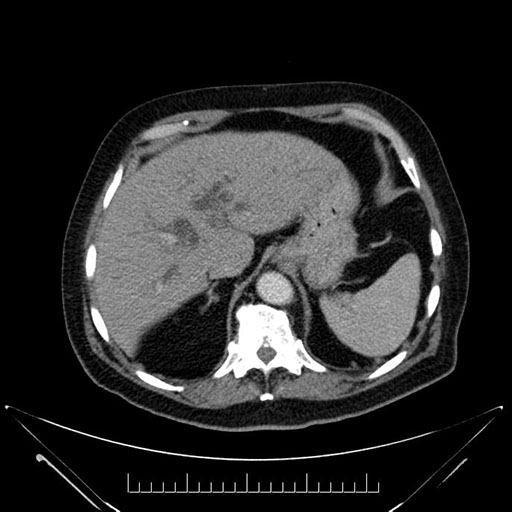

Axial - 3 months prior